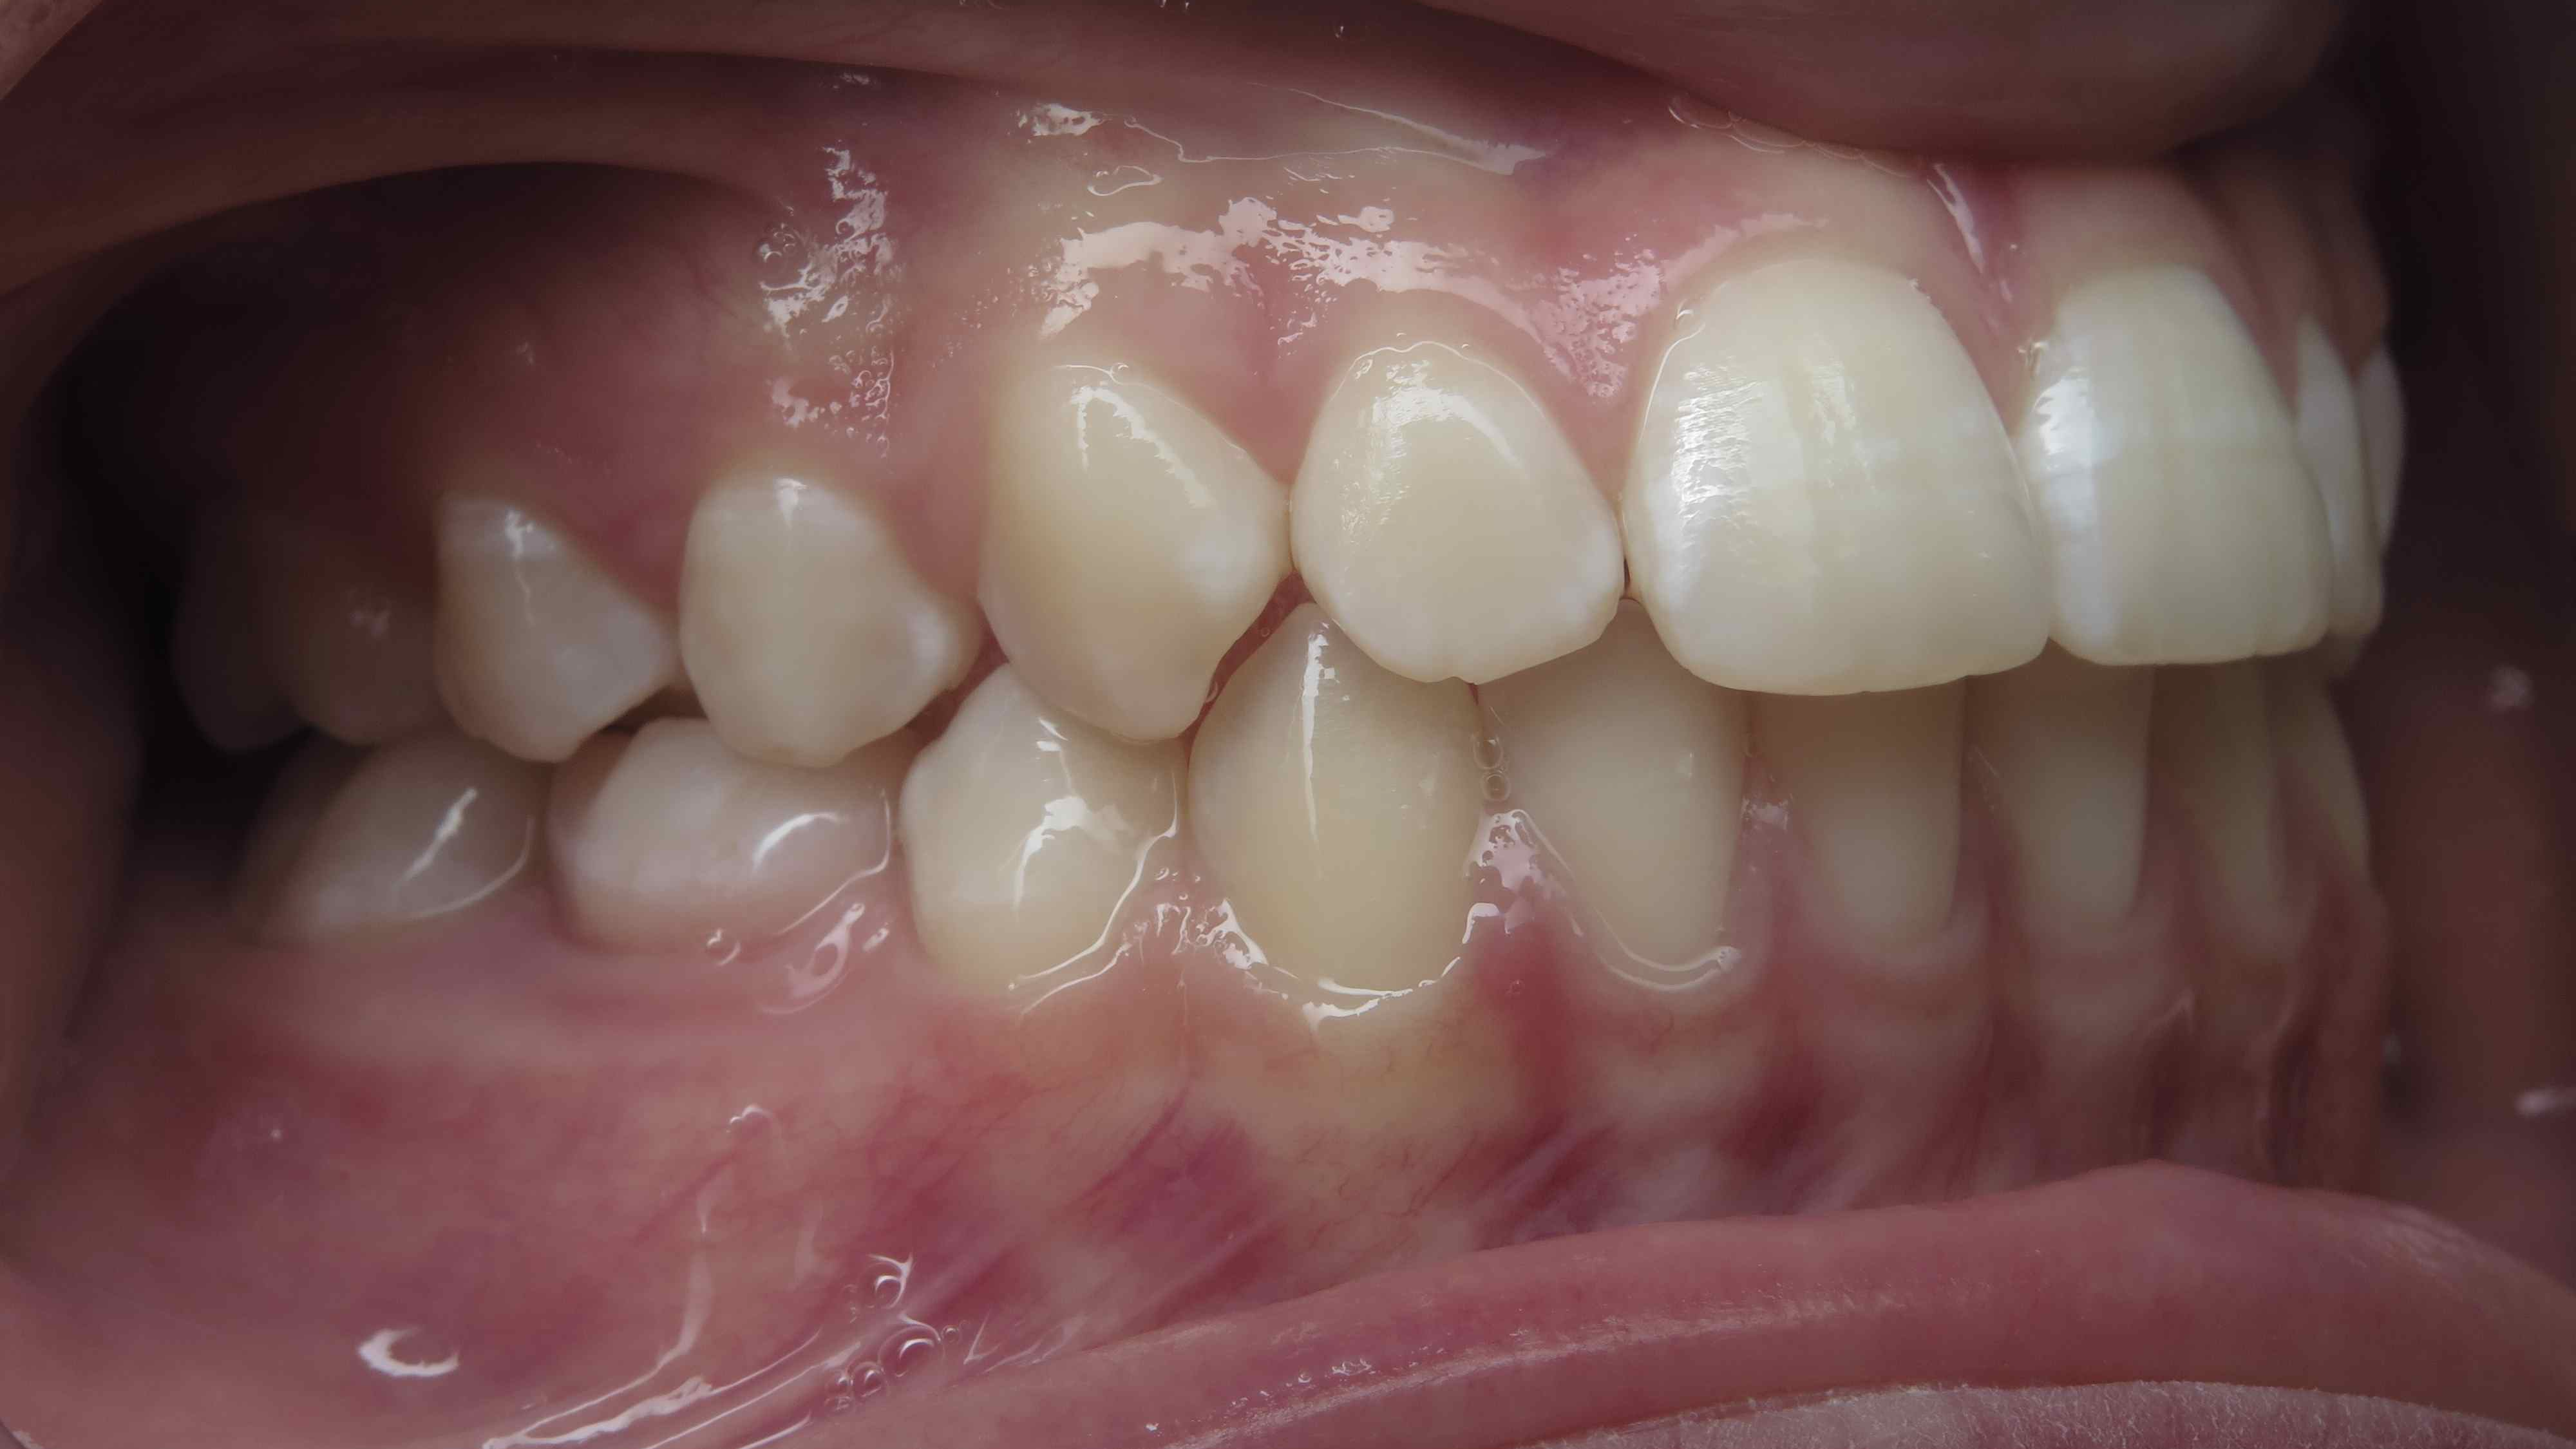

appareillage multibagues traitement en cours

bilan début et en cours de traitement